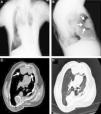

We report the case of a 61 year-old man, with a past history of bronchiectasis and severe restrictive ventilatory defect due to thoracic scoliosis (Fig. 1 A), who came to the pulmonology outpatients department with complaints of asthenia over the last year. He was an occasional pipe smoker and the physical examination showed marked thoracic deformity which limited chest expansion. A chest X-ray showed a large retrosternal opacity (Fig. 1B) and the chest computed tomography (CT) confirmed the presence of a retrosternal lobulated mass, 10.2cm×3.7cm, in the right hemithorax (Fig. 1C and D). A percutaneous CT-guided biopsy was carried out and the histology showed evidence of mesenchymal neoplasm without necrosis, significant pleomorphism or mitotic figures. The tumor cell population stained diffusely for CD 34, vimentin, bcl-2 and CD 99 and negative for S-100. Ki-67 was <5%. Although a benign SFTP was diagnosed based on the histology, a right thoracotomy was performed for diagnosis and treatment. A pedunculated tumoural mass was complete resected with segmental resection of the right upper lobe. Immunohistochemistry showed positivity for CD-34 and bcl-2 confirming SFTP. The pathological examination revealed multiple mitotic figures (12 mitoses per 10 high-power fields), mild pleomorphism, hypercellularity, focal hemorrhage and several areas of necrosis and the resection margins were tumor-free. According to these features the tumor was classified as malignant. The post-operative period was uneventful and the patient was discharged home. The patient is now in the third month after surgery without any sign of local recurrence or metastization.